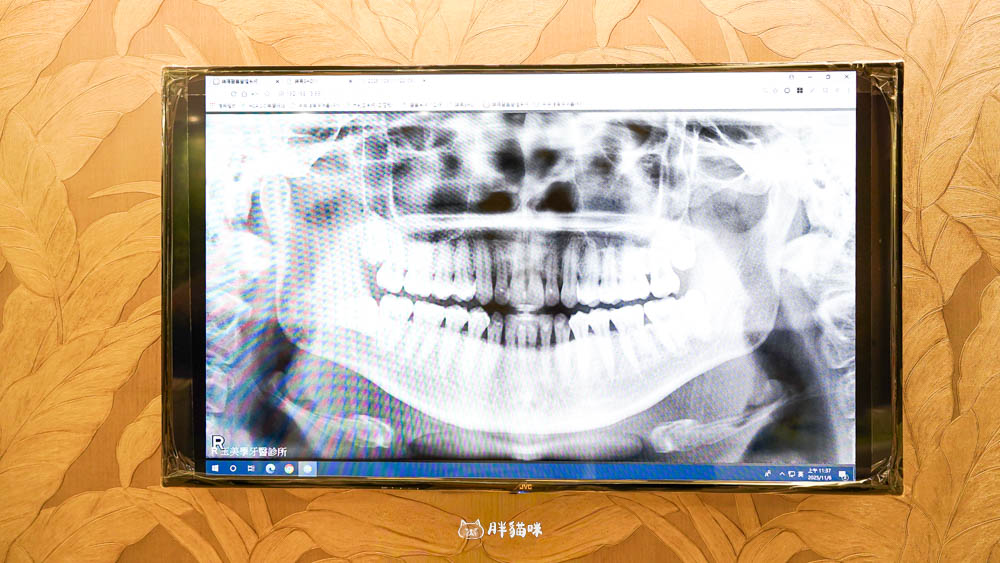

- 會請你進去拍個 X 光(這樣醫師才能看到牙齒縫隙有沒有問題)。

最後有個小小的警訊要提醒大家~醫師透過 X 光片,發現我牙齒接縫處有一些蛀牙!天啊,真的不能輕忽。

醫師也語重心長地提醒,一定要定期檢查牙齒的健康,不然很容易得牙周病,最後牙齒掉光光就糟糕了…我還有好多美食要吃耶!所以我已經預約下次要來把蛀牙補起來了。